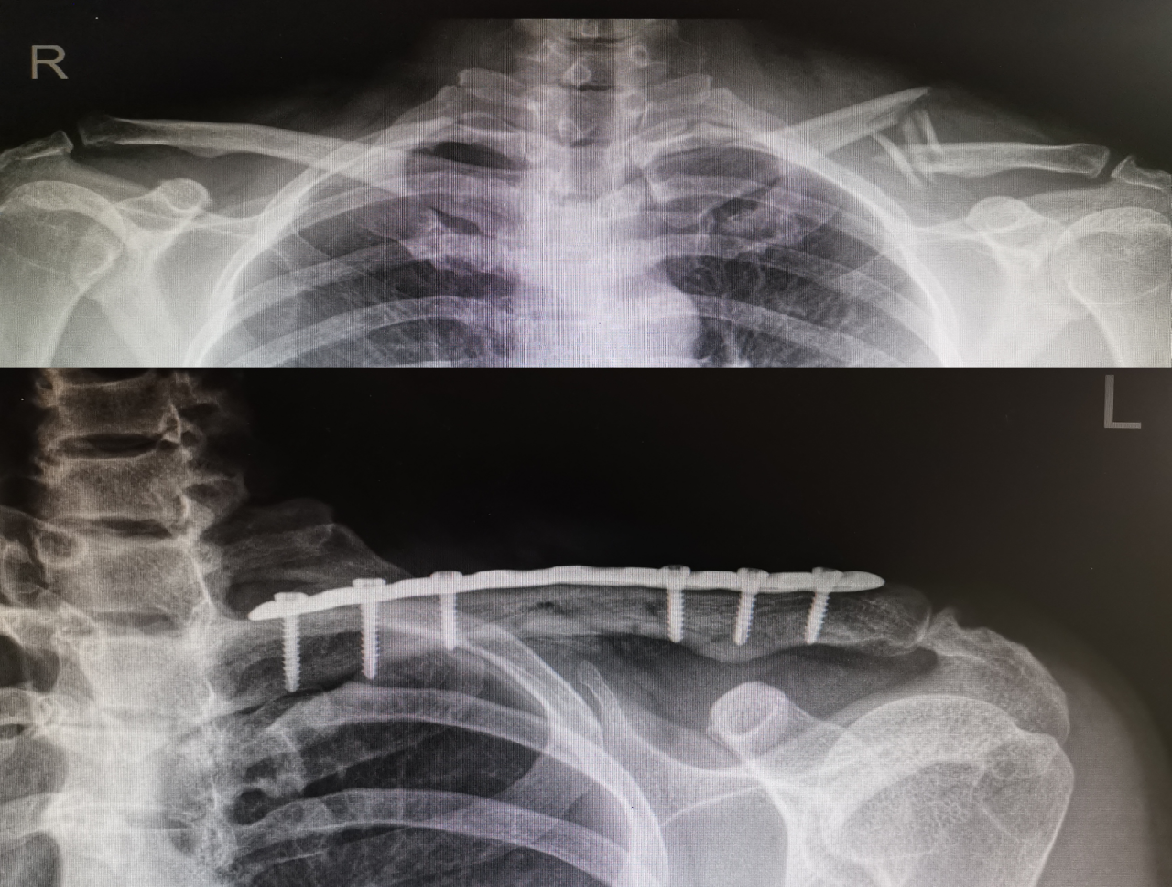

儿童锁骨骨折手术治疗 大于12岁 好大夫在线

一文掌握 锁骨骨折的固定及手术技巧都在这了 医学界 助力医生临床决策和职业成长